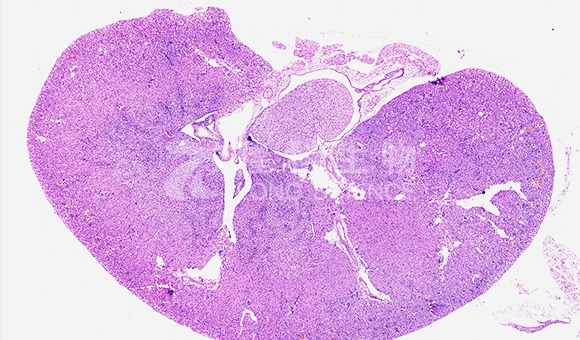

HE染色的原理是通过血红素和伊红与组织中的不同成分结合,使它们呈现出不同的颜色。血红素是一种天然染色剂,它与细胞核中的DNA结合,使细胞核呈现出深蓝色或紫色。伊红是一种酸性染料,它与细胞质和胞外基质中的碱性成分结合,使其呈现出粉红色或红色。

完成上述步骤后,HE染色的组织切片可以在显微镜下观察和分析,细胞核呈现深蓝色或紫色,细胞质和胞外基质呈现粉红色或红色,从而提供了组织的整体结构信息。